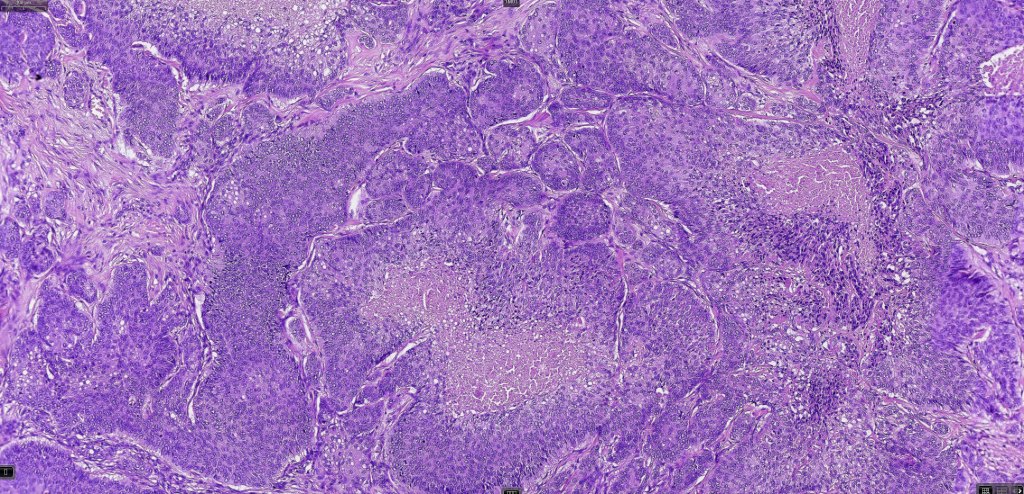

Histological features

•Well differentiated lobular growth pattern though to a poorly differentiated tumor often showing a diffuse, infiltrating border which may extend into the subcutaneous fat

•Peripheral palisading with retraction artifact and mucin deposition as seen in basal cell carcinoma is not present

•Comedo type necrosis commonly present

•Tumors are composed of an admixture of darkly staining basaloid cells with hyperchromatic or vesicular nuclei and more obvious sebaceous cells with eosinophilic, bubbly, multivacuolated cytoplasm frequently indenting the nucleus (scalloped)

•Often mitoses are numerous and abnormal forms evident

Sebaceous carcinoma from a patient with Muir-Torre syndrome kindly shared by Dr. Antonina Kalmykova.